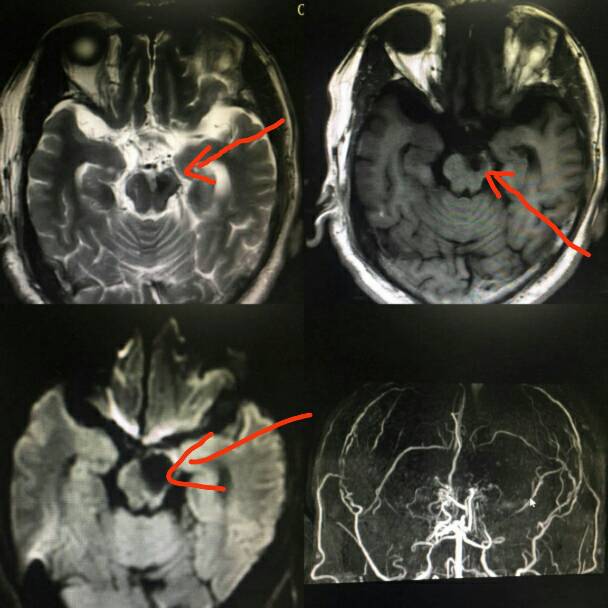

图为颅内大动脉动脉瘤弹簧圈栓塞后3.0T磁共振图像。图片来自南京鼓楼医院